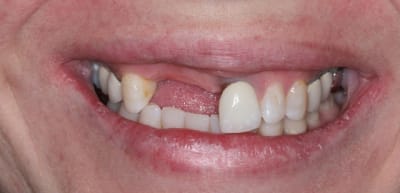

On avance dans le cas, j'ai revu la patiente hier.

Elle est satisfaite et moi pas vraiment, comme quoi...

Elle ne veut pas faire de chir mucco gingivale et accepte éventuellement que je fasse une petite chir d'élongation coronaire sur 21 car elle trouve cela surperflux.

Tristesse et difficulté des sourires gingivaux !

J'avais bien raison de me méfier au départ...

Dommage pour la teinte...

Une greffe osseuse aurait bcp aider, les implants sont trop enfouis par rapport à la 21.

Je suis persuadé que si ton prothèsiste réussit à reproduire la richesse des petits défauts de ses propres dents sur tes dents en céramique , ce serait et ça passerait bcp mieux

Je crois que finalement ces trois trop jaune et quasi monolithique ds leur couleur est vraiment la chose la plus atroce

Une petite plastie gingivale sur 21 22 et des belles Céram et hop ça devient super top !